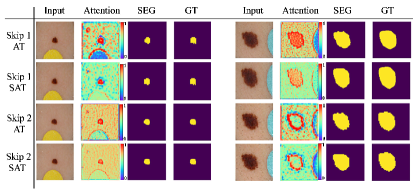

Note also that, although sometimes ST obtained almost similar results to SAT, the SAT transfers only one channel whereas ST results in transferring multiple channels (i.e. ST requires more parameters and involves higher memory usage). Similar to SAT, AT also transfers only one channel, however, as shown in Figures 6 and 7, AT tends to attend to wrong regions as it does not leverage the ST module to filter the most discriminative channels.

After the selected channels are transferred to the attention layer, the model learns to attend to the most important part(s) of the image, which helps in segmenting the target object(s) more accurately. A few samples of the attention maps for two of the proposed skip connections, used within the 2D U-Net (Fig. 6) and 3D V-Net (Fig. 7) architectures, are shown in Figs. 6 and 7 for the 2D skin lesion and 3D prostate MRI datasets. As can be seen in both Figs. 6 and 7, a model with only attention layer (i.e., only AT) tends to attend to several areas of the image; including both where the object is present and absent (note the red colour visible over the whole image). However, applying channel selection (i.e., ST) before the attention layer curtails the model from attending to less discriminative regions.

Advantages of channel selection and attention. For some experiments, we observed slight improvement in terms of Dice score when comparing the proposed method vs. only channels selection (or attention), but we argue that there are clear advantages in combining channel selection and attention because: 1) channel selection reduces the number of feature maps and more importantly enforces learning sparse representations, 2) channel selection alone outputs many channels which require more memory and more parameters to learn whereas the proposed method transfers only one channel (which is more interpretable) thus reducing number of network parameters and memory usage, 3) attention after the selection helps focusing on the most important spatial regions in the input, which is not captured by the channel selection part, however, attention without channel selection tends to attend to wrong areas as visualized above (Figures 6 and 7).